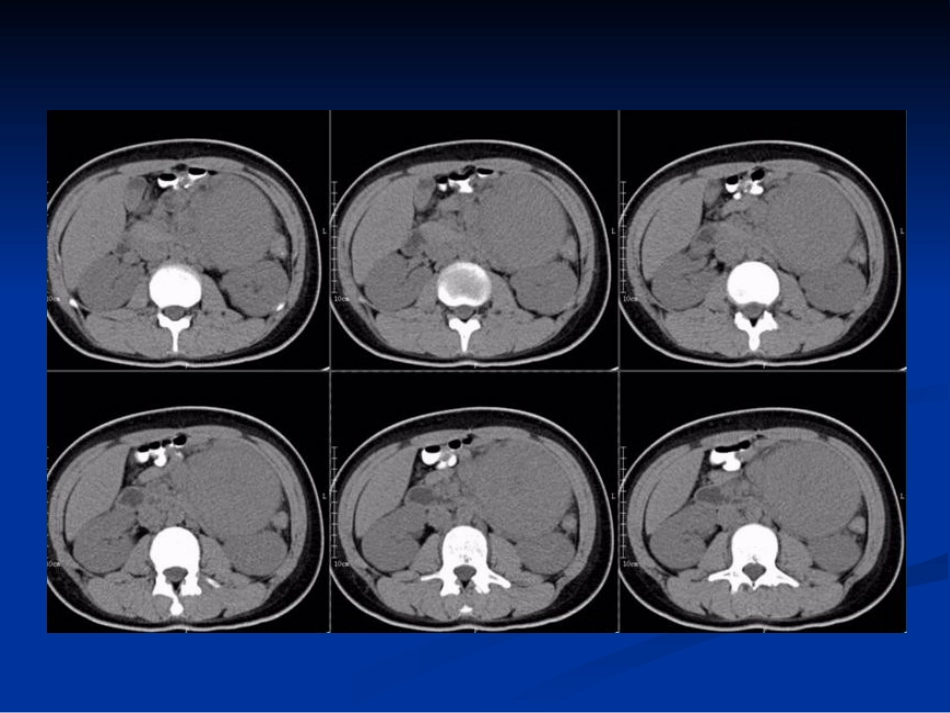

病例一病例一男,男,1616岁,无明显诱因出现左上腹疼痛,岁,无明显诱因出现左上腹疼痛,呈阵发性绞痛,每次发作持续约呈阵发性绞痛,每次发作持续约1-21-2分钟后分钟后自行缓解,无呕吐、腹泻、黑便,肛门排气、自行缓解,无呕吐、腹泻、黑便,肛门排气、排便正常。排便正常。左上腹触及一约左上腹触及一约10×10cm10×10cm大小包块,质大小包块,质硬,边界清,活动度尚可,压痛阳性,肠鸣硬,边界清,活动度尚可,压痛阳性,肠鸣音正常。音正常。彩超:左上腹低回声肿块,边界清,内部回彩超:左上腹低回声肿块,边界清,内部回声不均,其内及周边可见丰富血流信号。声不均,其内及周边可见丰富血流信号。病例二病例二患者女,患者女,3232岁,体检发现右纵隔旁肿物。岁,体检发现右纵隔旁肿物。家族史:有两人死于肺癌。家族史:有两人死于肺癌。??巨淋巴结增生症巨淋巴结增生症巨淋巴结增生症巨淋巴结增生症(GLNH)(GLNH)是一种少见病,是一种少见病,病因尚不明确,患者多无症状,为异源性病因尚不明确,患者多无症状,为异源性的罕见的淋巴组织增生性疾病,亦称为血的罕见的淋巴组织增生性疾病,亦称为血管滤泡性淋巴组织增生。管滤泡性淋巴组织增生。GLNHGLNH于于19541954年由年由CastlemanCastleman首先发现,故又称其为首先发现,故又称其为CastlemanCastleman病。病。19561956年确定为良性非肿瘤性病变。年确定为良性非肿瘤性病变。发病与病因发病与病因GLNHGLNH自自19541954年发现以来,关于年发现以来,关于GLNHGLNH的病因尚存在两种不同的学说的病因尚存在两种不同的学说::第一种认为本病表现为反应性淋巴组织增第一种认为本病表现为反应性淋巴组织增生,与慢性抗体刺激有关,可能为病毒感生,与慢性抗体刺激有关,可能为病毒感染所致。染所致。第二种理论则认为透明血管型是一种淋巴第二种理论则认为透明血管型是一种淋巴组织的进行性生长紊乱,而浆细胞型的发组织的进行性生长紊乱,而浆细胞型的发生与生与IL-6IL-6调节障碍有关。调节障碍有关。病理病理在病理上可分为透明血管型和浆细胞型两种类型在病理上可分为透明血管型和浆细胞型两种类型透明血管型:特征为淋巴滤泡退化和毛细血管数透明血管型:特征为淋巴滤泡退化和毛细血管数量增加。突出的变化有:肿胀的血管内皮、外皮量增加。突出的变化有:肿胀的血管内皮、外皮细胞以及生发中心内的少量网状细胞可排列成同细胞以及生发中心内的少量网状细胞可排列成同心圆样结构,血管壁周围有透明样物沉着,并发心圆样结构,血管壁周围有透明样物沉着,并发生纤维化和玻璃样变。生纤维化和玻璃样变。浆细胞型:病理显示为滤泡增生,其中心含有大浆细胞型:病理显示为滤泡增生,其中心含有大量核分裂相和组织细胞,滤泡间可见成片成熟或量核分裂相和组织细胞,滤泡间可见成片成熟或不成熟的浆细胞,偶有组织细胞、淋巴细胞和免不成熟的浆细胞,偶有组织细胞、淋巴细胞和免疫母细胞渗入浆细胞中。疫母细胞渗入浆细胞中。临床表现临床表现GLNHGLNH中透明血管型最为常见,约占发病中透明血管型最为常见,约占发病率的率的76%76%~~91%91%,而浆细胞型则较少见。,而浆细胞型则较少见。GLNHGLNH按其临床、影像学表现及其预后亦按其临床、影像学表现及其预后亦分为分为22型型::局限型和弥漫型。局限型和弥漫型。局限型:多为透明血管型,表现为孤立淋局限型:多为透明血管型,表现为孤立淋巴结或某一组淋巴结受累。巴结或某一组淋巴结受累。弥漫型:多为浆细胞型,多为一组以上的弥漫型:多为浆细胞型,多为一组以上的淋巴结受累。淋巴结受累。局限型临床多无症状局限型临床多无症状,,为体检或常规胸片偶尔发现为体检或常规胸片偶尔发现,,可见于任何年龄可见于任何年龄,,发病高峰为发病高峰为3030岁~岁~4040岁之间岁之间,,女性约女性约44倍于男性倍于男性,95%,95%以上为透明血管型以上为透明血管型,,手术手术多可切除多可切除,,预后良好。预后良好。弥漫型通常有临床症状与体征弥漫型通常有临床症状与体征,,包括发热、乏力、包括发热、乏力、贫血、表浅淋巴结肿大、肝脾肿大、血沉...